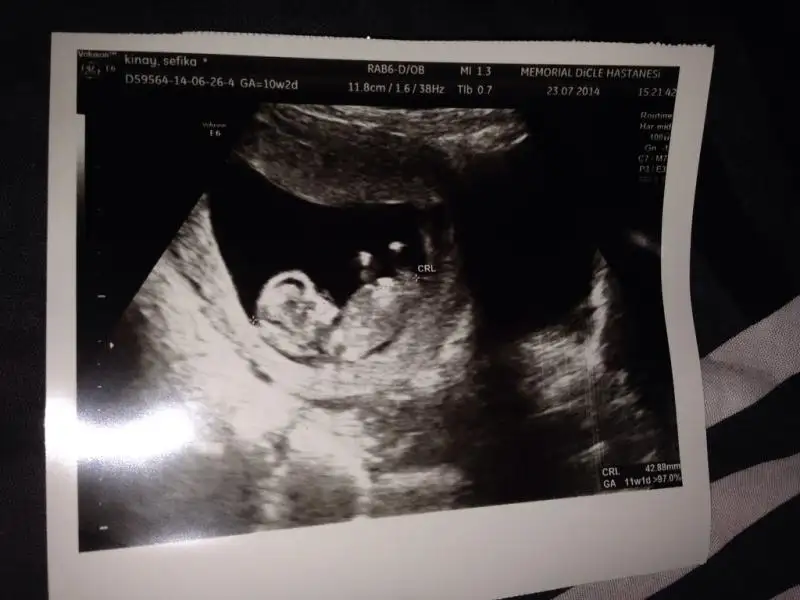

benim bugün ikili testim vardı ense kalınlığı 1.1 mm olarak ölçtü doktor kan testimde çıkmış bu ne demek oluyor. yaptıranlar bi yorumlayıversin iyimi. internetten baktım normal gözüküyor ama

-PAPP-A 5.32

-SERBEST BETA-HCG 23.3

Ense kalınlığı iyi canım bide Allah bilir tabi ama seninde oğlun olacak tabi sağlıklı olsunda

Eki Görüntüle 1200851 Eki Görüntüle 1200852

Yorumları alalım :)

iPhone 'den Kadınlar Kulübü aracılığı ile gönderildi

Masallah:nazar: kuzucuga sağdaki renkli ultrason mu

Evet :) aslında 12. Haftadan önce açmıyoruz dedi de doktor, açtı sonra. 11+ 1 miş. Hadi kızlar cinsiyet tahmini alalım ;)